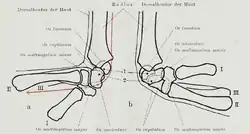

Labelled image showing the eight carpal bones. | |

There are four groups of ligaments in the region of the wrist:[8]

- The ligaments of the wrist proper which unite the ulna and radius with the carpus: the ulnar and radial collateral ligaments; the palmar and dorsal radiocarpal ligaments; and the palmar ulnocarpal ligament. (Shown in blue in the figure.)

- The ligaments of the intercarpal articulations which unite the carpal bones with one another: the radiate carpal ligament; the dorsal, palmar, and interosseous intercarpal ligaments; and the pisohamate ligament. (Shown in red in the figure.)

- The ligaments of the carpometacarpal articulations which unite the carpal bones with the metacarpal bones: the pisometacarpal ligament and the palmar and dorsal carpometacarpal ligaments. (Shown in green in the figure.)

- The ligaments of the intermetacarpal articulations which unite the metacarpal bones: the dorsal, interosseous, and palmar metacarpal ligaments. (Shown in yellow in the figure.)